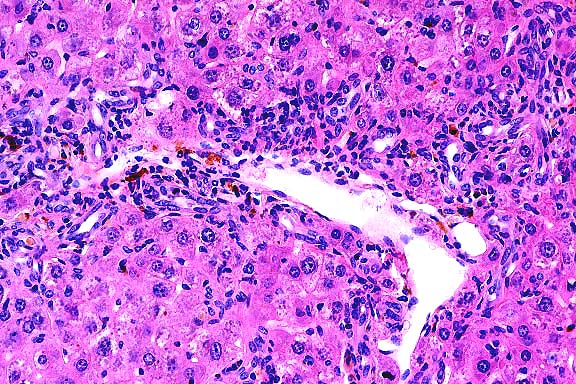

20x

obj

- Case 19-2. Thymus. There is diffuse, marked depletion

of lymphocytes and no distinction between cortical and medullary

zones. Reticular stromal cells remain with few small lymphocytes.

- AFIP Diagnoses:

- 1. Thymus and lymph node: Hypoplasia, lymphoid, diffuse,

severe, Jack Russell terrier, canine.

- 2. Thymus and lymph node: Extramedullary hematopoiesis, diffuse,

mild to moderate.